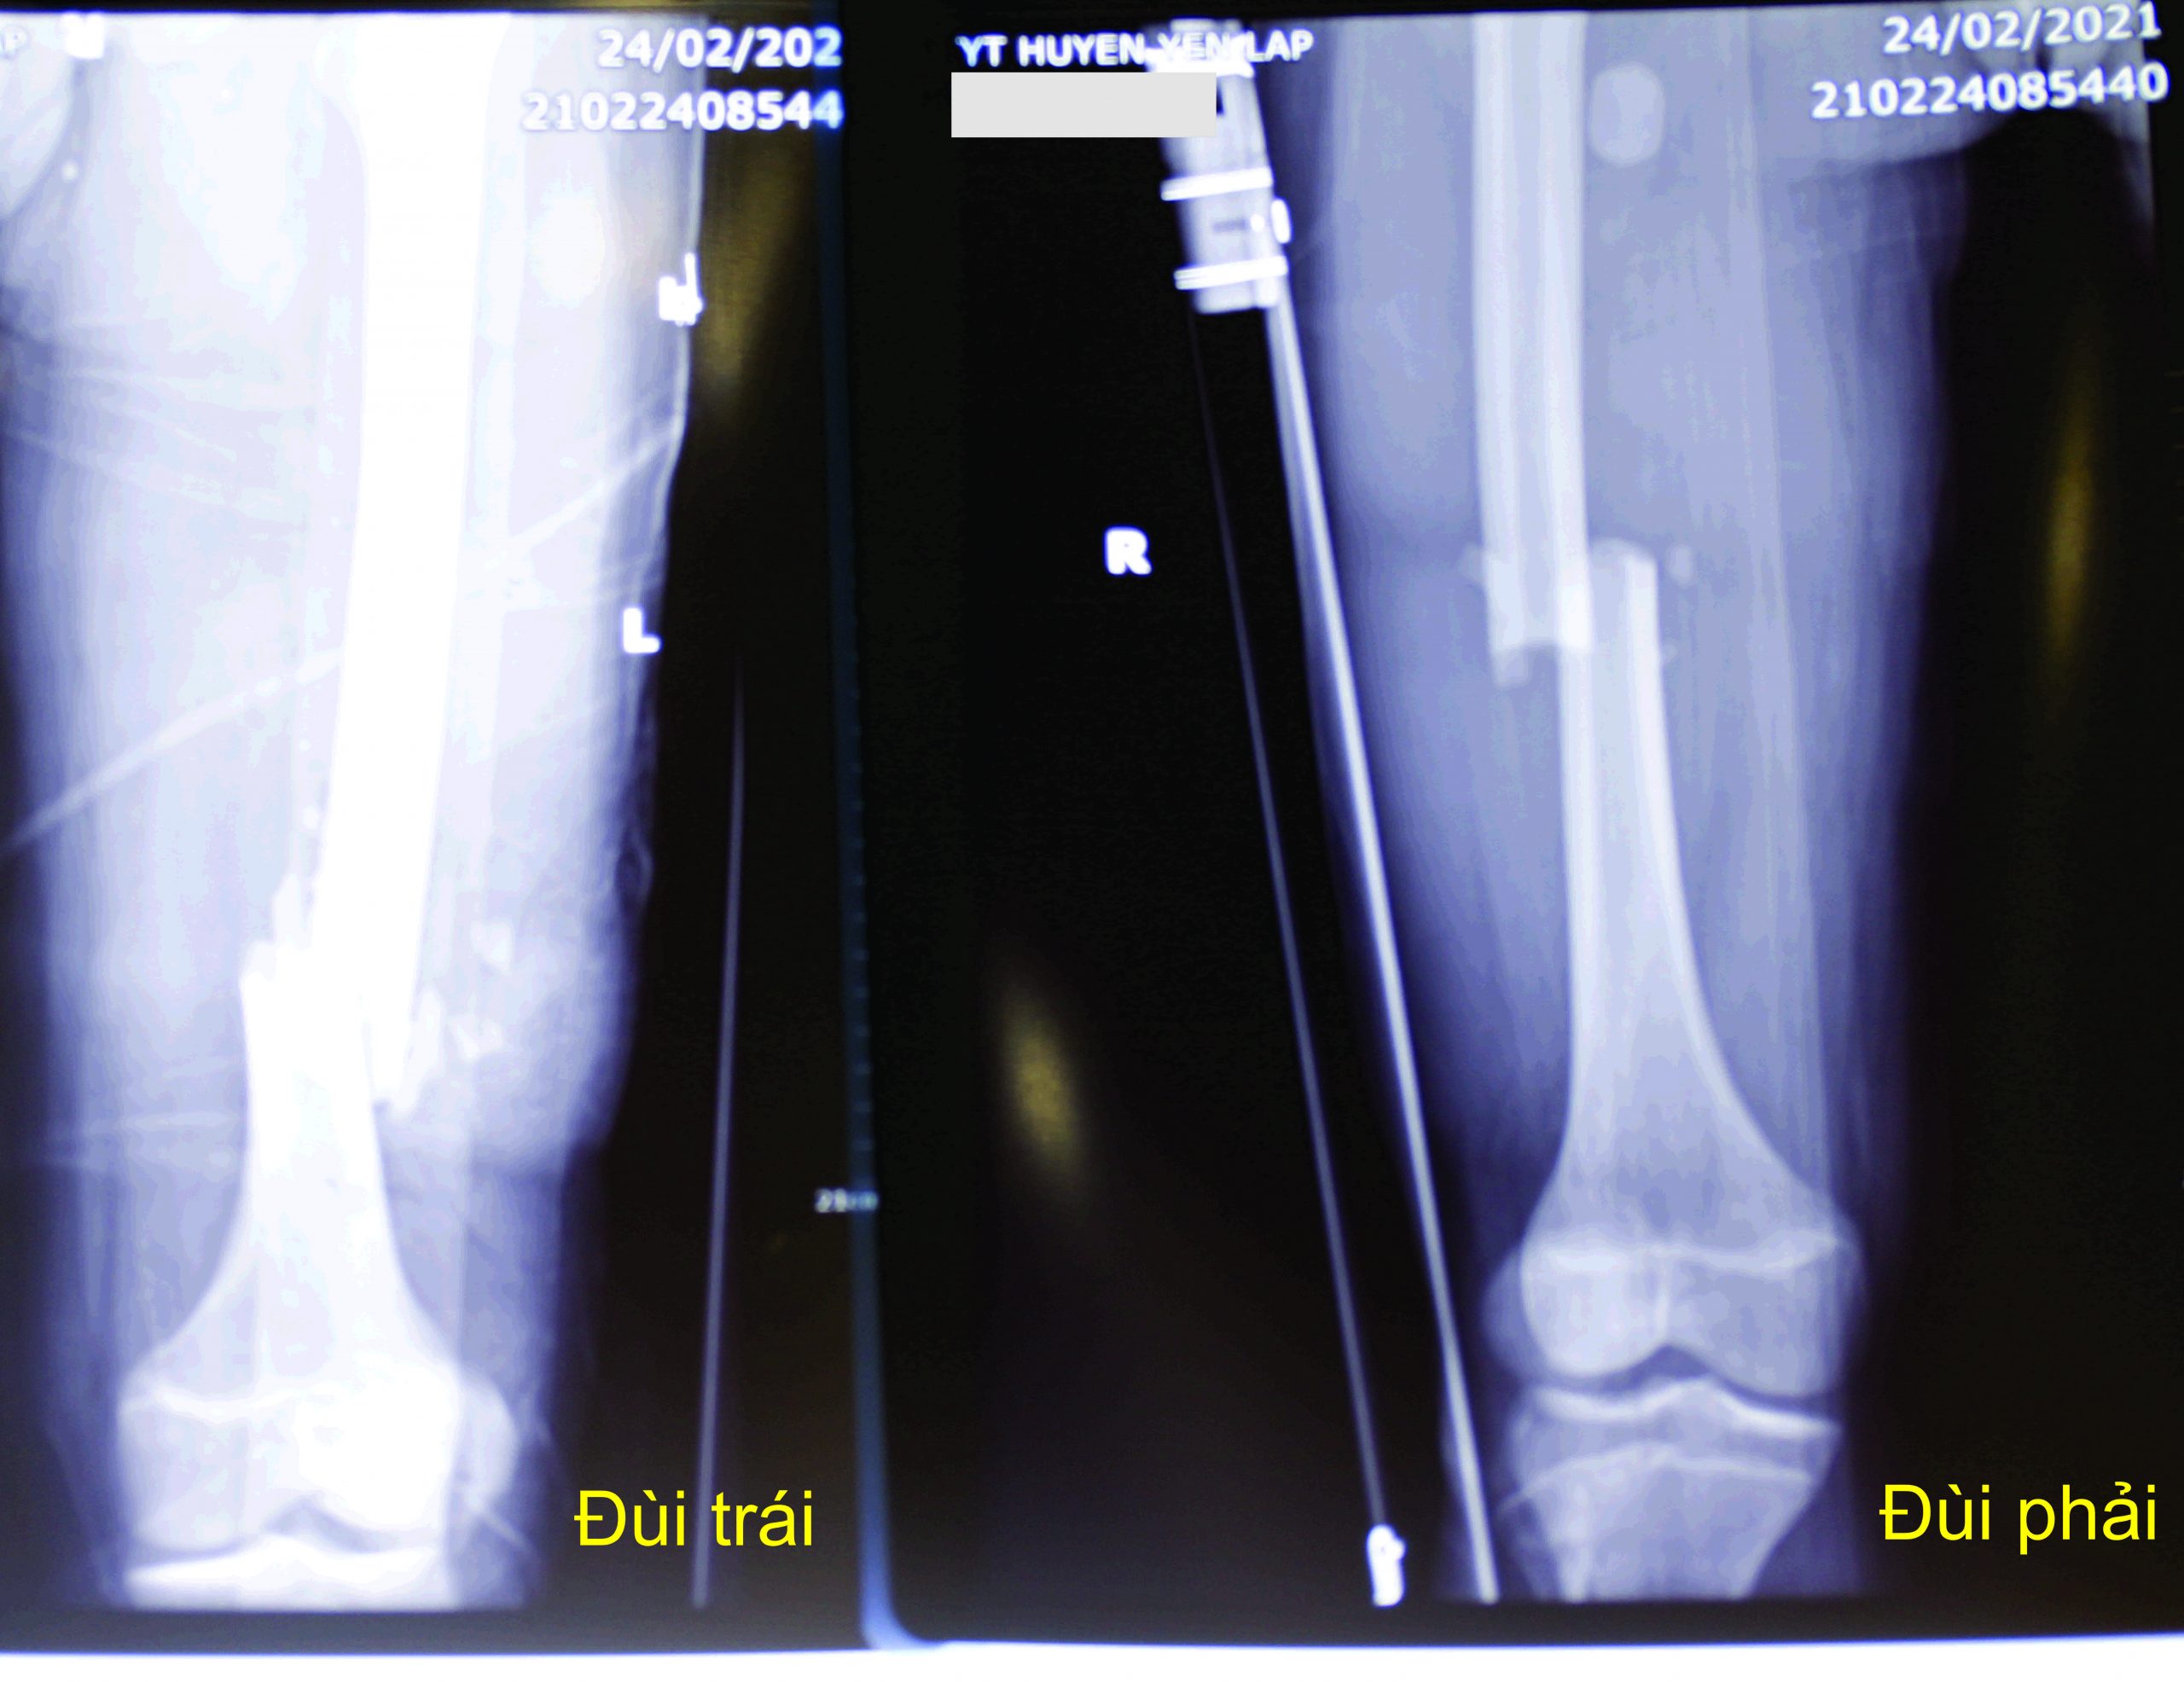

Tại Trung tâm Y tế huyện Yên Lập, bệnh nhân được chỉ định thực hiện các cận lâm sàng: chụp cắt lớp vi tính, X-quang xương đùi hai bên, siêu âm, xét nghiệm. Kết quả thể hiện trên hình ảnh cho thấy bệnh nhân bị gãy hở 1/3 xương đùi trái, gãy kín 1/3 xương đùi phải.